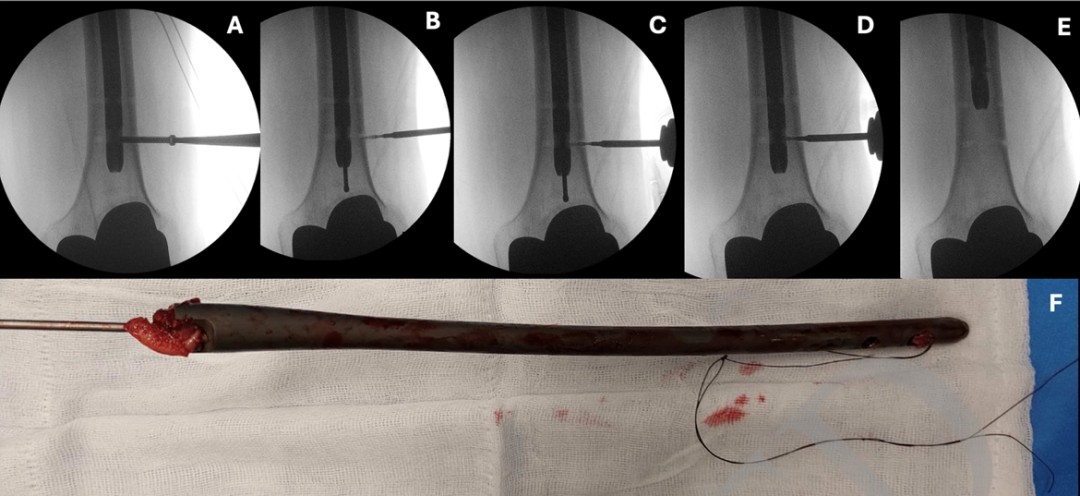

本技术所需设备见表1。应用前提是:断裂部分至少保留一个完整的圆形锁定孔,且孔内最好仍有锁定螺钉(图2A)。若无可用锁定孔,需徒手钻取远端锁定孔。

经原切口显露髓内钉进针点。连接T形手柄,将橄榄头导丝送入断裂钉远端,直至遇锁定螺钉受阻。取出该螺钉后继续推进导丝,使其超出钉端1–2厘米。

根据髓内钉芯直径及导丝直径选择合适螺钉,使其能在导丝原位状态下置入锁定孔。4毫米锁定孔推荐使用直径2毫米螺钉,5毫米锁定孔则使用2.4毫米螺钉。螺钉长度不应超过髓内钉直径。

用2-0缝线系住微型螺钉头部以防脱落,在透视引导下将其旋入或敲入锁定孔(图2C)。螺钉就位后回抽导丝,使其与螺钉嵌合(图2D),随后敲击T形手柄将导丝连同断裂髓内钉一并取出(图2E)。操作中需持续保持导丝张力,以防螺钉脱落。关键步骤见表2,技术细节见补充视频。